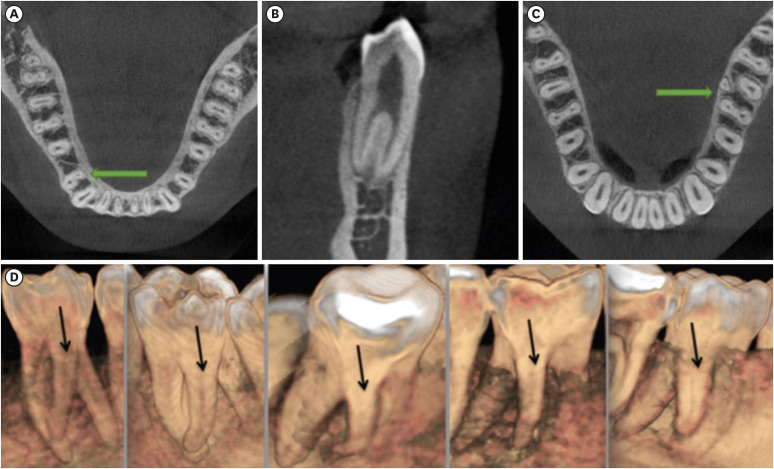

• 4. Mandibular premolars (Figure 3A and 3B) [8]:

• Single canal.

• Complicated canal: exhibiting multiple canals and roots.

• 5. MnFMs (Figure 3C and 3D) [8]: These teeth were categorized as 2-rooted and 3-rooted. Three-rooted teeth were considered to have a complicated root structure.

Figure 3

(A, B) Mandibular first premolar with complicated root canals, (C, D) examples of radix entomolaris in the mandibular first molar tooth.

rde-49-e2-g003.jpg